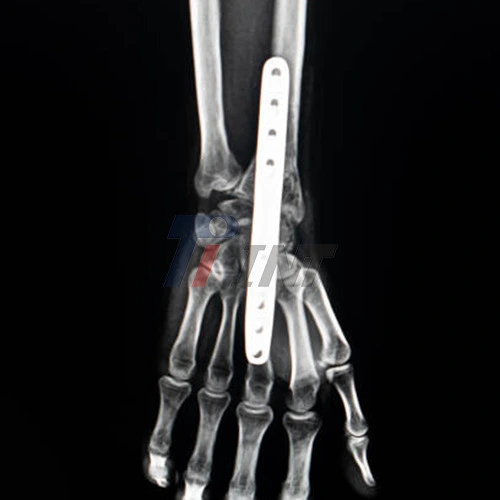

Titanium plates are often used in wrist surgery to provide stability and support during the healing process. These biocompatible implants are favored for their strength, durability, and ability to integrate with bone tissue. The use of titanium in medical procedures has revolutionized orthopedic surgeries, offering patients improved outcomes and faster recovery times.

During wrist surgery, surgeons may use titanium plates to:

- Stabilize fractured bones

- Correct deformities

- Support joint fusions

- Facilitate proper alignment of bones and joints

The type and size of the titanium plate in wrist surgery used will depend on the specific nature of your wrist condition and the surgical procedure being performed. Your surgeon will determine the most appropriate titanium implant based on your individual needs and the complexity of your case.